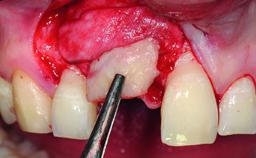

Replacement of an Upper Right Central Incisor with Root Resorption: Ridge Preservation, Delayed Placement of an NC Bone Level Roxolid Implant

A 32-year-old female Caucasian patient with a compromised maxillary right central incisor was referred to us by a general dentist. Her chief complaints were discomfort and mobility of tooth 11 with unsatisfactory esthetics due to discoloration. The patient reported a previous trauma, some years earlier, as the origin of pathology on the afflicted tooth. Anamnesis was negative for any other dental or periodontal pathology in the remaining dentition. The patient did not take any medication and reported to be a light smoker (5–10 cigs/day). She had high esthetic expectations of her treatment. The extraoral examination revealed a high smile line with full exposure of her maxillary teeth and surrounding soft tissue in the area between the second premolars.